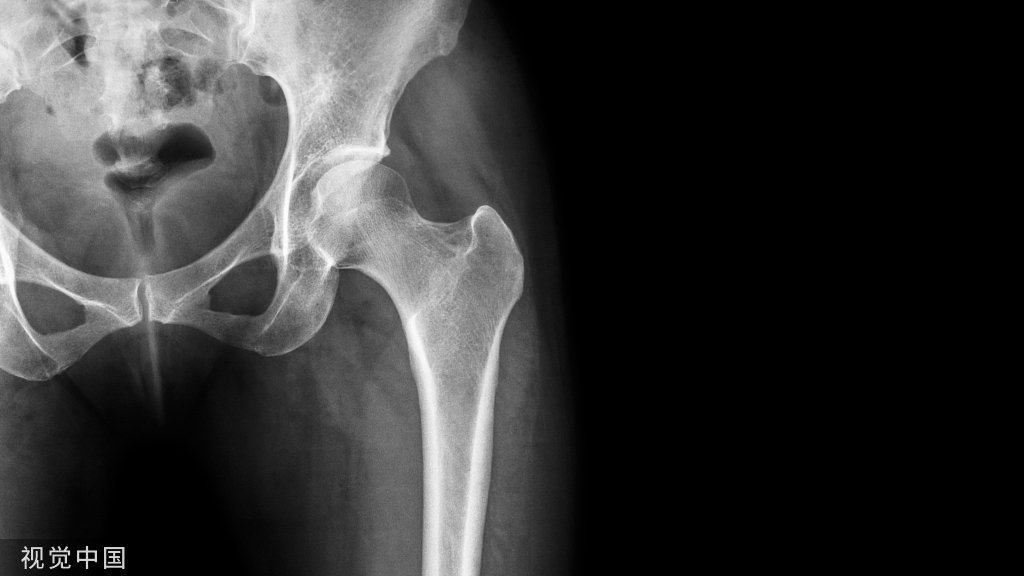

髂腰肌,系髋肌前群肌之一。由腰大肌和髂肌构成。腰大肌起自腰椎体的侧面和横突,髂肌起自髂窝。两肌相结合,经腹股沟韧带的深处下至髋关节的前面而止于股骨的小转子。此肌可屈与外旋大腿,下肢固定时使骨盆和躯干前屈。受腰丛肌支(胸12腰1—4)支配。